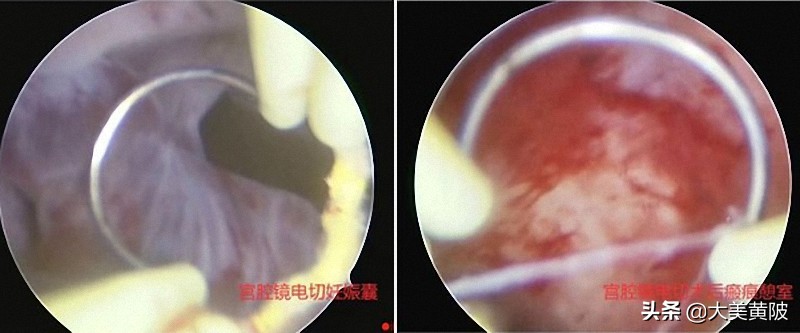

(上图)宫腔镜子宫瘢痕妊娠电切视野图

患者彭女士,28岁,因停经后阴道少许出血,于2月19日来区人民医院就诊,彩超提示宫腔下段及前壁切口区妊娠(3.0*0.7cm),考虑剖宫产瘢痕部位妊娠,收妇科入院治疗。本着生命至上,为患者提供个性化治疗的原则,妇科主任刘海琳确诊患者为剖宫产瘢痕部位妊娠后,立即请介入治疗室会诊。经与患者及家属充分沟通,提供三种治疗方案备患者选择,结合患者年龄及生育要求及CSP类型后,最终确定先行介入栓塞治疗暂时阻断子宫血供后再行宫腔镜检查+妊娠物电切术。介入治疗室王方明主任更是为了最大限度保障患者安全及手术的及时性,积极联系上级医院教授连夜加班为患者施行了介入手术。2月21日,行宫腔镜手术耗时15分钟顺利完成,术中术后出血总量少于50ML,术后第2天患者复查血HCG 已经降至220mIU/ml(术前12111.64 mIU/ml)。患者目前已经康复出院随诊。